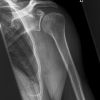

Schwedenstatus (3 Aufnahmen)

1. Aufnahme:

Patient steht mit dem Rücken am Stativ, gesunde Seite mit 45° Keil angehoben, Arm und Ellenbogen um 90° angewinkelt, Handinnenfläche am Körper angelegt. (Innenrotation)

2. Aufnahme:

Gleiche Stellung des Patienten, jedoch Unterarm nach vorne drehen (Neutralstellung), d.h. 45° zum Stativ, Arm zeigt in Richtung Fußspitze.

3. Aufnahme:

Patient steht mit flach angelegtem Schulterblatt am Stativ, Oberarm 90° abduziert und maximal nach außen rotiert, Ellenbogen um 90° gebeugt (Daumen zeigt zum Stativ), wie 2. Ebene der Schulter in der Medizin, Kopf zur gesunden Seite drehen.

1. und 2. Aufnahme:

Trifft 15-20° cranio-caudal auf Oberarmkopf.

Senkrecht auf Oberarmkopf. Oberer Kassettenrand: 2 Querfinger oberhalb der Hautgrenze.

Indikation

Bei Verdacht auf Fraktur des Tuberculum major, nach Luxation und Periathritis, bei Impressionsfraktur nach Luxation, was bei normalen Schulteraufnahmen nicht diagnostizierbar sind.

Qualitätskriterien

Freie Darstellung des Gelenkspaltes.

1. Aufnahme: Tuberculum majus und minus nebeneinander dargestellt.

2. Aufnahme: Besonders deutlich kommt hier die obere Facette des Tuberculum majus zur Darstellung.

3. Aufnahme: Nahezu überlagerungsfreie Darstellung des Humeruskopfes und Durchblick durch das Humeroglenoidalgelenk.